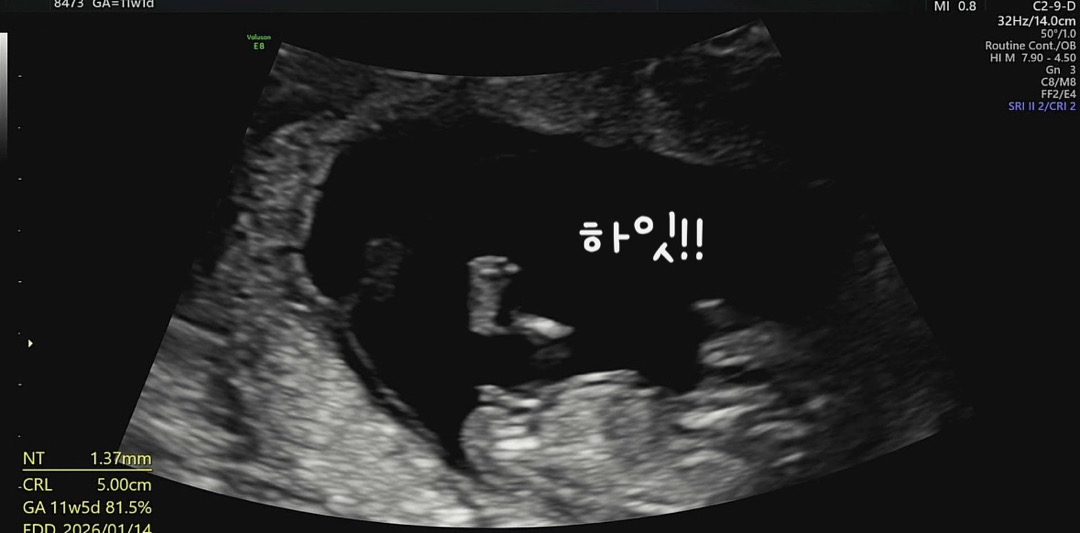

딸같아요!!

저도 각도법 좀 봐주시면 안될까요..?👉🏻👈🏻

참견 부탁드려요..ㅎㅎㅎ👏🏻

저도 딸이였음 좋겠어용 ㅎㅎ

딸에한표요!